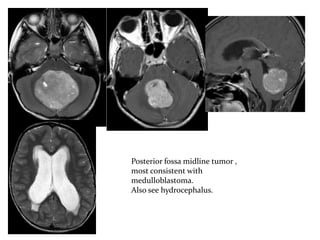

Posterior fossa midline tumor ,

most consistent with

medulloblastoma.

Also see hydrocephalus.

Posterior fossa midlinetumor , most consistent with medulloblastoma. Also see hydrocephalus.